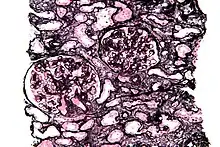

Micrograph of a kidney biopsy stained with a Jones stain.

It stains for basement membrane and is widely used in the investigation of medical kidney diseases.

The Jones stain demonstrates the spiked GBM, caused by subepithelial deposits, seen in membranous nephropathy.